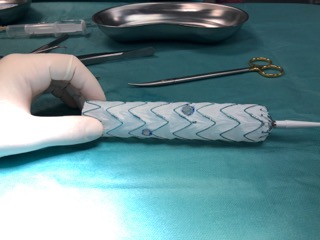

Bezinwazyjne, skuteczne leczenie nietrzymania moczu

2024-04-16Wysiłkowe nietrzymanie moczu dotyczy obu płci i zdarza się w każdym wieku. Jednak częściej dotyka kobiety, co ma związek z przebytymi ciążami i porodami, i występuje u co piątej z nich. Tymczasem lekarze Klinicznego Oddziału Ginekologii Rekonstrukcyjnej i Onkologicznej USK-2 uczyli się stosować metody nowatorskiego leczenia nietrzymania moczu.

W wysiłkowym nietrzymaniu moczu (WNM) tzw. złotym standardem jest stosowanie taśm – syntetycznych siatek. Chociaż problem zdawał się być rozwiązany, dochodzi jednak czasami do powikłań, które nierozłącznie związane są z leczeniem chirurgicznym. Przy zbyt ciasnym założeniu taśmy dochodzi do tzw. mikcji przeszkodowej, kiedy oddawanie moczu jest utrudnione, a przy zbyt powierzchownym założeniu taśmy - powstają dokuczliwe dla pacjenta w leczeniu erozje (ekspozycja w taśmy w ścianie pochwy). Możliwe są również uszkodzenia pęcherza moczowego, cewki moczowej czy nawet krwiaki.

Dr n. med. Piotr Kolczewski, ginekolog z Klinicznego Oddziału Ginekologii Rekonstrukcyjnej i Onkologicznej chce na szczecińskim oddziale wprowadzić możliwość nowatorskiego leczenia, od lat stosowanego z powodzeniem na świecie, szczególnie w Wielkiej Brytanii. To preparat urolon, który przezcewkowo, w znieczuleniu miejscowym podawany jest w celu „uszczelnienia” cewki moczowej. Będzie to pierwsze zastosowanie tej metody w publicznej placówce zdrowia.

Preparat podawany jest pod kontrolą cystoskopu (co daje duży poziom precyzji podania leku) – długą, miękką igłą, w okolice tzw. połączenia cewkowo-pęcherzowego. Zabieg polega na wykonaniu ok. 3 nakłuć oraz podaniu preparatu (ok. 1-3 ml), uszczelniającego światło cewki moczowej. Wyniki takiego leczenia są obiecujące, a ewentualne powikłania obserwowane są na poziomie 3% i dotyczą przejściowej, wymagającej jedynie krótkotrwałego cewnikowania mikcji przeszkodowej.

Pierwsze warsztaty pn. „Okołocewnikowa iniekcja preparatu urolon w leczeniu wysiłkowego nietrzymania moczu” w Klinicznym Oddziale Ginekologii Rekonstrukcyjnej i Onkologicznej USK-2 odbyły się 21 marca 2024 roku. Preparat został skutecznie podany trzem pacjentkom, u których zdiagnozowano WNM.

W warsztatach wzięli udział lekarze Oddziału, a także lekarze z innych ośrodków ginekologicznych w Polsce, m.in. w Poznaniu czy Warszawie. Poprowadził je dr Nabil Elmahdawi z Londynu, mający wieloletnie doświadczenie w stosowaniu tej metody.